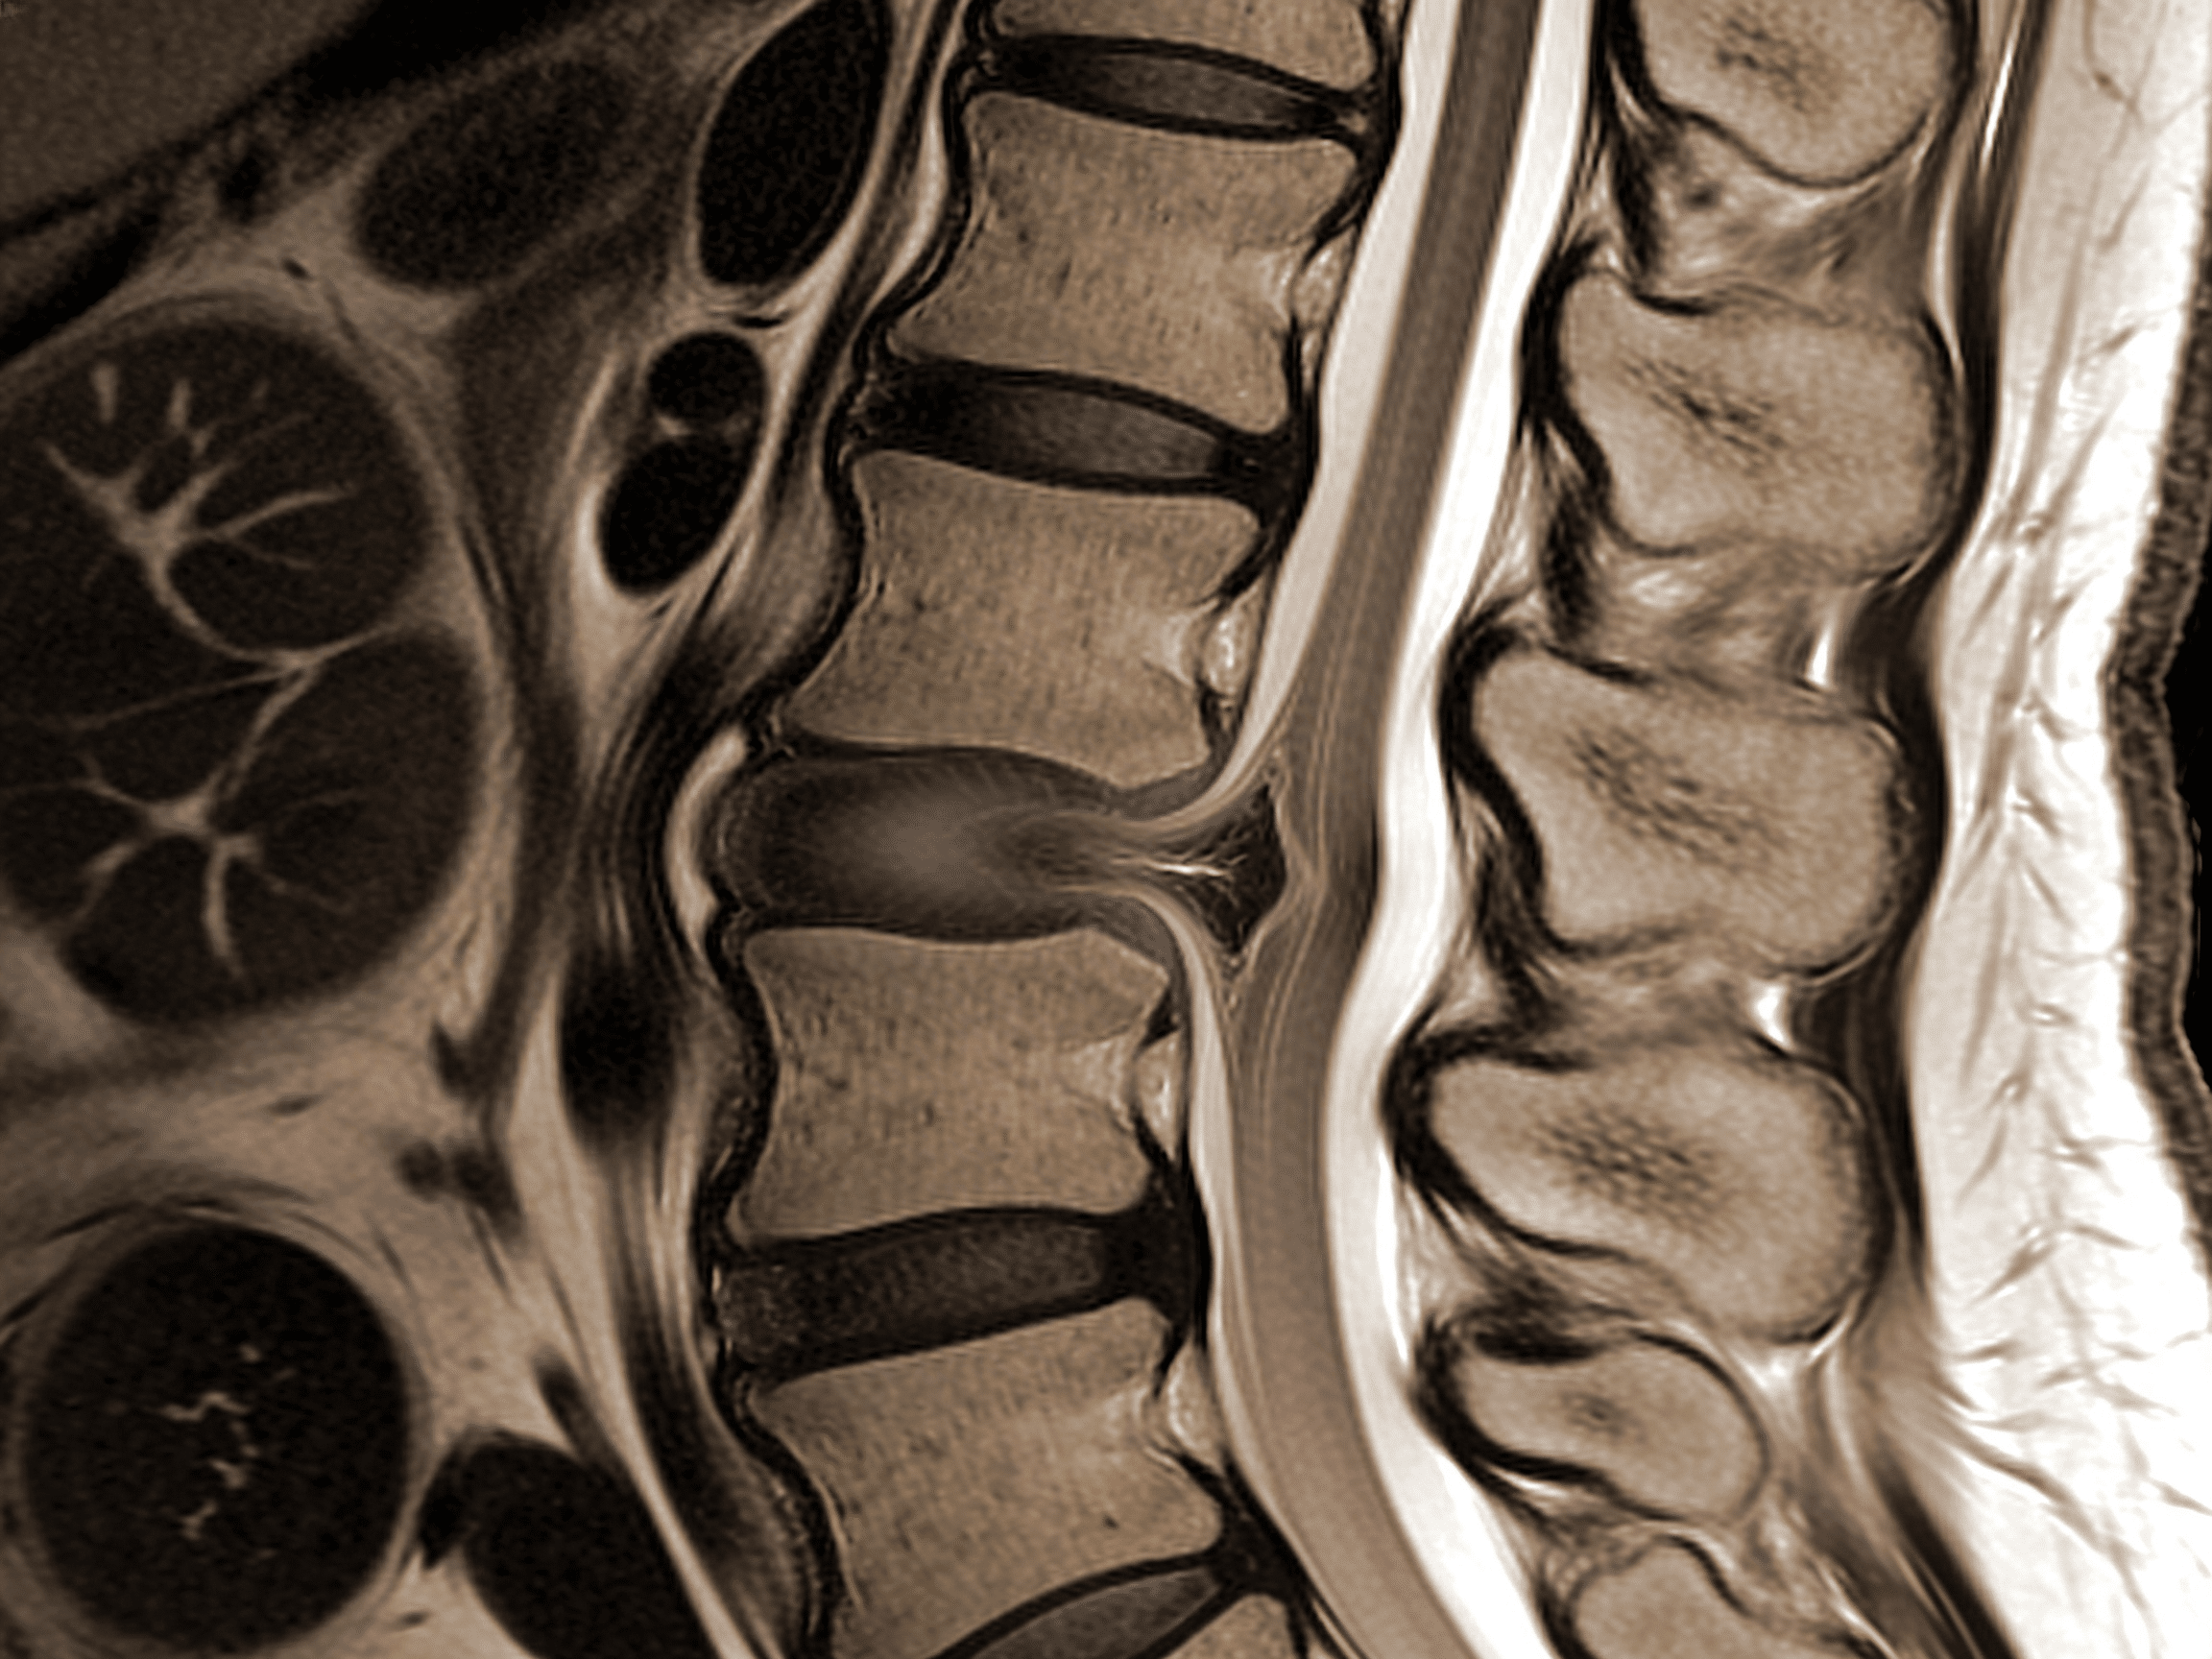

Priority ER's diagnostic capabilities for MRI spine for cord compression or acute back injury exceed Joint Commission standards for emergency departments[14], featuring immediate coordination with affiliated MRI facilities providing stat imaging within 2 hours, 1.5T or 3T MRI scanners with sagittal T1, T2, and STIR sequences visualizing cord signal changes indicating injury (T2 hyperintensity suggesting edema or myelomalacia), and immediate radiologist interpretation identifying disc herniation, hematoma, tumor, or abscess causing cord compression with 93% sensitivity. Our emergency physicians trained in spinal imaging interpretation apply Canadian C-Spine Rules and NEXUS criteria determining which patients require imaging, perform detailed neurological examination using ASIA impairment scale (motor scores 0-5 in key muscles, sensory testing in dermatomes), and initiate methylprednisolone within 8 hours when incomplete cord injury identified on MRI improving neurological recovery by one ASIA grade[15]. The integration of diffusion-weighted imaging (DWI) identifies acute epidural abscess appearing as restricted diffusion, while gadolinium contrast enhancement differentiates tumor from infection and identifies vascular malformations causing cord compression.

Advanced assessment through our comprehensive diagnostic capabilities provides CT myelography when MRI contraindicated by cardiac pacemaker or retained metallic fragments, performing lumbar puncture injecting iodinated contrast outlining spinal cord and detecting compression with 88% sensitivity comparable to MRI. For cervical spine clearance, our emergency physicians apply validated decision rules (NEXUS criteria: midline tenderness, altered consciousness, intoxication, distracting injury, neurological deficit) determining when imaging unnecessary in low-risk patients, while high-risk mechanisms (diving, axial load, high-speed collision) trigger comprehensive CT and MRI evaluation. This comprehensive approach explains why the American College of Radiology appropriateness criteria mandate MRI as gold standard for suspected cord compression, providing superior soft tissue visualization compared to CT identifying epidural collections, ligamentous injury, and cord signal changes invisible on CT requiring MRI for definitive diagnosis guiding neurosurgical decision-making.

Can CT scan replace MRI for diagnosing spinal cord compression?

No, CT visualizes bone excellently but cannot adequately assess spinal cord, intervertebral discs, ligaments, or epidural collections causing compression. Priority ER performs CT spine initially identifying fractures and bony canal compromise, then coordinates MRI when neurological deficits suggest cord compression from soft tissue (disc, hematoma, tumor, abscess) invisible on CT. MRI remains gold standard with 93% sensitivity for cord compression versus 45% for CT, providing T2-weighted images showing cord edema and contrast-enhanced sequences differentiating tumor from infection guiding neurosurgical treatment decisions.